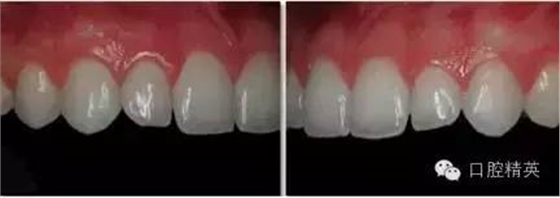

上前牙照

正面觀

1:1 (1:1.5)放大倍率

需要使用拉鉤

•上前牙應位于照片中央,用中線及唇系帶作為參照點平分照片。人中在此視角中應無法暴露。

•照片的中線應水平平分中切牙(請勿使用切平面作為水平中線)。

•拉鉤不應出現在此圖中。照片中的齦緣應清晰可見。

•下頜牙不應出現在此視角中。

•可以使用背板拍照。如使用背板,應避免出現陰影。

•在患者的正前方拍照,相機應與被拍攝物成90°。

•在1:1 (1:1.5)視圖中,只能拍到4~6顆牙齒。

側面觀

•側切牙應位于照片中央,縱向平分照片。

•照片的中線應水平平分側切牙(請勿使用切平面作為水平中線)。

•相機應與側切牙唇面成90°角放置。

•近相機處的拉鉤應盡量向后牙區(qū)域牽拉,遠相機處的拉鉤應盡量向遠離牙齒的方向牽拉。